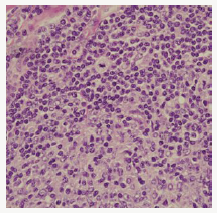

Composite lymphoma as an entity was initially described by Custer et al followed by a modified delineation by Hicks et al and Kim et al with a categorical emergence of architecturally diverse and binary cytological subcategories of lymphoma within the same anatomic site or tissue. Composite lymphoma as a disorder essentially describes a biphasic elucidation of an identical malignant clone of cells [1]. A discordant lymphoma may be exemplified by a condition in which two disparate lymphomas may arise at different anatomic locations within an identical time frame (Figure 1). Sequential lymphoma may be characterized by the appearance of two distinctive histological variants of malignant lymphoma detected successively within a similar group of lymph nodes.

Figure 1:CL: small and large B cell zones with cellular pleomorphism [13].